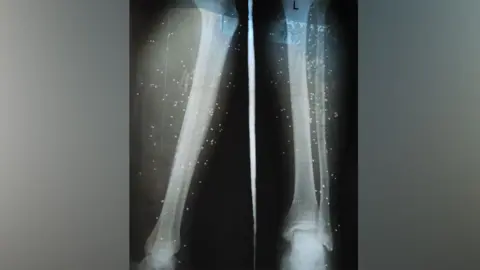

X-rays showed birdshot embedded in the legs of a wounded protester

They stayed at the couple's home until it was almost dawn and then managed to find a doctor they knew, who cleaned the birdshot wounds on their legs, according to Tara.

She said a surgeon was later able to remove some of the birdshot at home but warned them: "They cannot all be removed and will remain in your bodies."